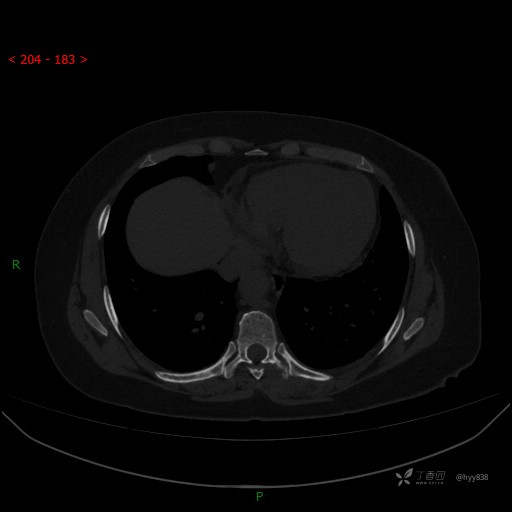

胸部CT平扫